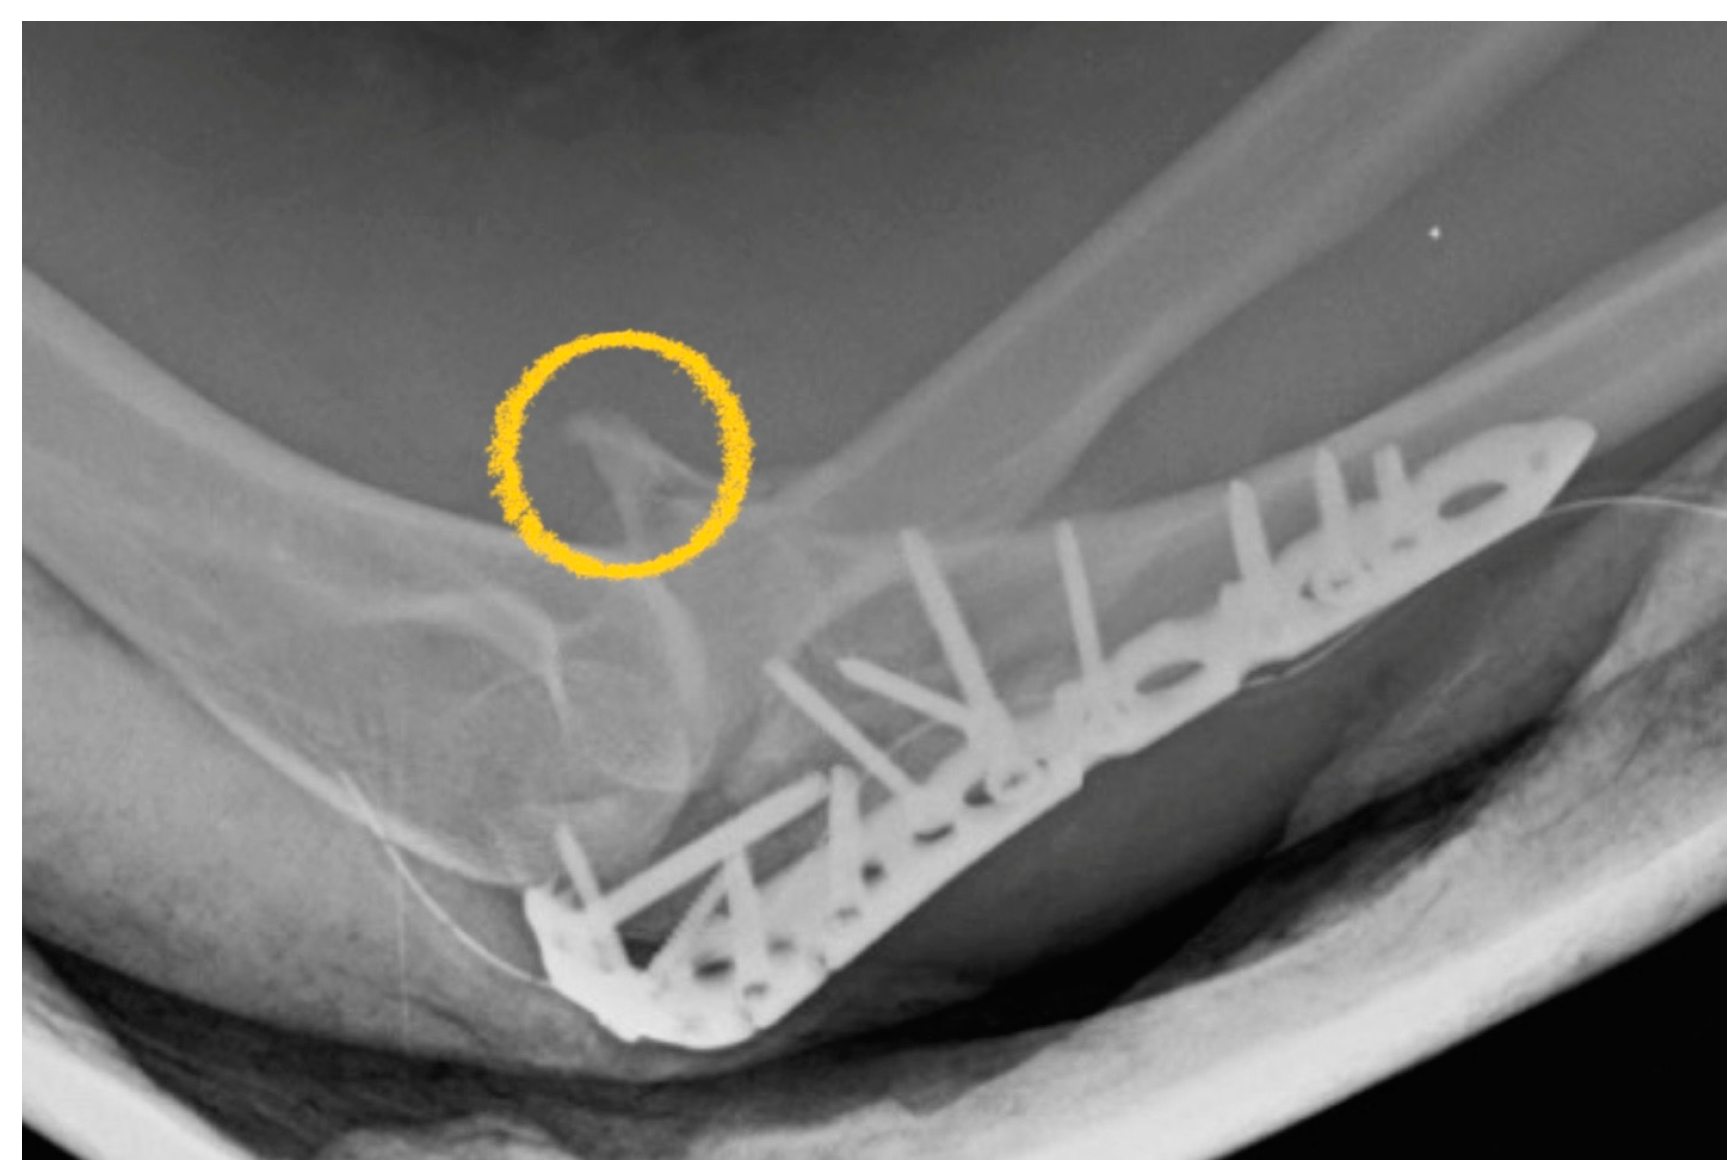

2.3. Fixation of Radial Head

2.4. Variant Proximal Ulnar Fractures and Ligaments Injuries